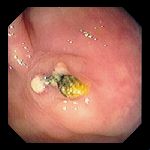

Внешний вид швов, сохранившихся после операции на ободочной кишке. Часто имеется сопутствующая воспалительная реакция (обратите внимание на очаговый эксудат на фото#1). Иногда реакция имеет полиповидную форму (фото#3), имитируя неоплазию.